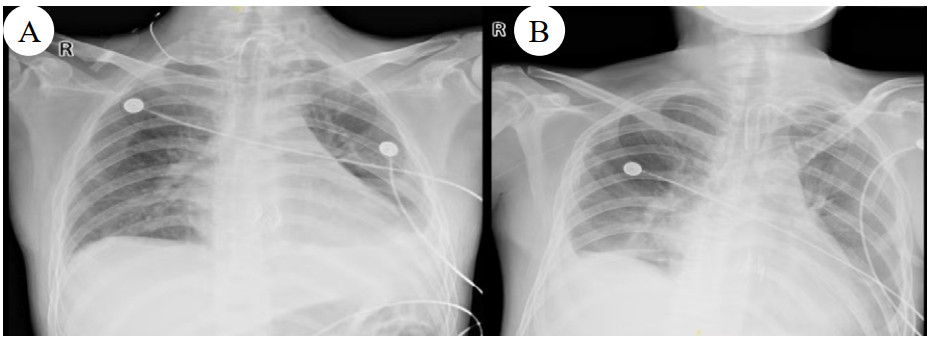

1 病例资料2024-11-15,某工地操作间有值班人员3人,分别为上铺(距地面1.8 m)A某,下铺(距地面0.4 m)B某、C某,事发当天为午休时间,设备出现故障,下午14时维修人员D某进入操作间维修,并将门窗打开,完成维修操作;事发后24 h内4名患者均出现不同程度的恶心、呕吐等消化道症状,起初考虑可能与食物中毒有关,前往当地医院就诊,完善血便常规、胸腹CT等相关检查未见明显异常,在医院给予吸氧补液静卧留观,留观期间4人先后出现不同程度的咽痛、咳嗽、胸闷、憋气等不适,吸氧不能缓解,再次行胸部CT检查示双肺弥漫性改变,间质改变可能,考虑为吸入有毒有害气体,后经采样检测操作间气体残留为全氟-4-甲基-2戊稀[Perfluoro(4-methylpent-2-ene),D1](D1纯度99.92%),导致急性呼吸窘迫综合症(acute respiratory distress syndrome, ARDS)。参照2002年职业性急性有机氟中毒诊断标准[1],A某诊断为急性中度有机氟气体中毒,B某、C某、D某诊断为急性重度有机氟气体中毒(PaO2/FiO2 < 100 mmHg,1 mmHg=0.098 kPa)。立即给予大剂量(120 mg)甲泼尼龙琥珀酸钠治疗,同时补充多种微量元素,加用甲钴胺、硫辛酸,钙剂解毒,后续加用特殊解毒剂乙酰胺治疗。治疗1周后,上铺的A某胸闷、憋气症状较前好转,影像未见明显进展,但患者仍遗留有间断气短症状;其余人员病情持续恶化,出现呼吸衰竭,转入重症医学科,给予气管插管接呼吸机辅助通气,维修人员D某上呼吸机后能基本维持,但不能脱机,继续观察患者病情变化;而下铺患者B某、C某症状不断加重,即使给予呼吸机治疗低氧状态仍未见明显改善,于2024-11-29转入本院进一步治疗。B某、C某入本院时查体:双肺叩诊呈清音,双肺呼吸音粗,可闻及干湿性啰音,具体指标见表 1,图 1、2为肺部影像进展情况。入院给予镇静镇痛、机械通气及抗感染、抗炎、抑酸等治疗,呼吸困难仍持续加重,存在难以纠正的低氧血症及高碳酸血症,表现为ARDS,有体外膜肺氧合(extracorporeal membrane oxygenation, ECMO)治疗指征,参考国内外相关救治经验[2-6],给予患者静脉-静脉ECMO(veno-venous extracorporeal membrane oxygenation, V-V ECMO)治疗,具体参数见表 2。

| 图 1 B某发病第1、3、10天胸部CT |